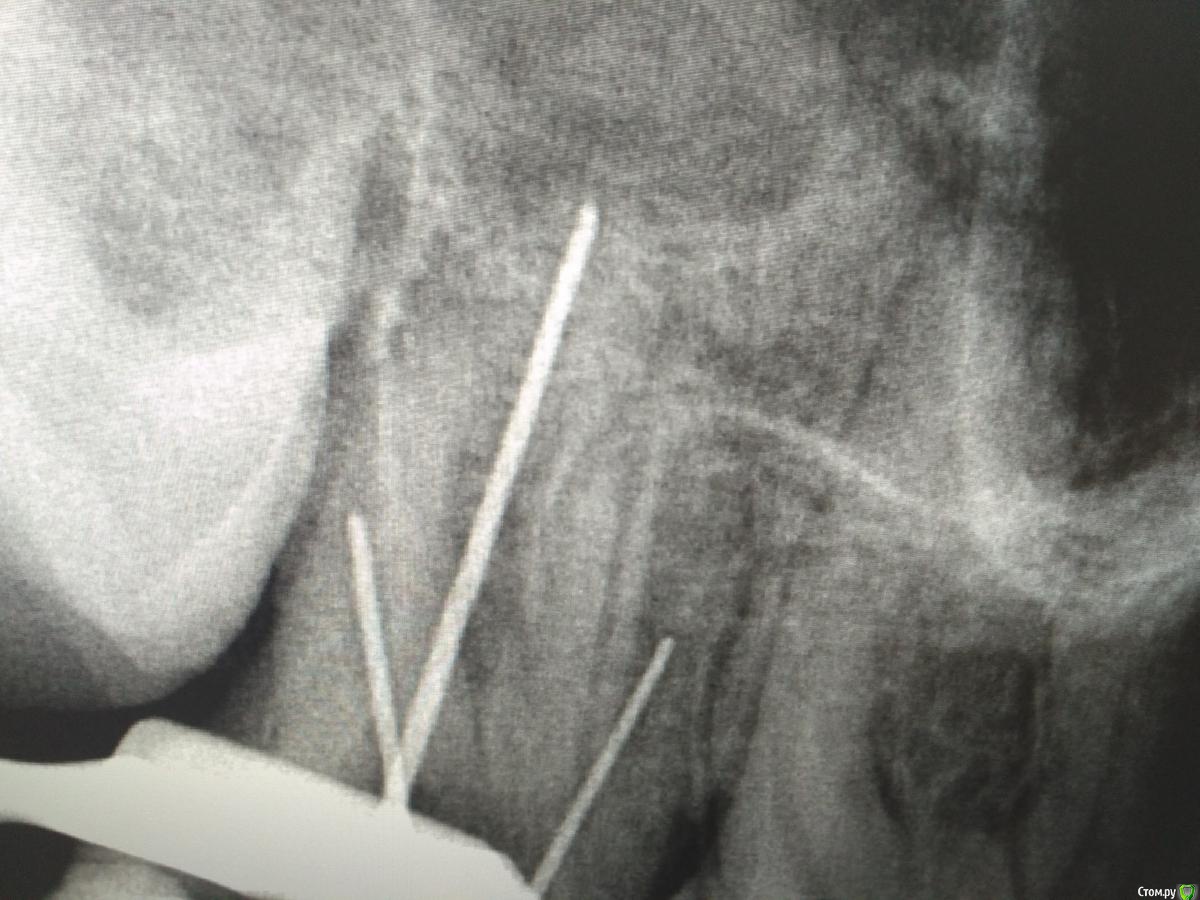

St. Опубликовано 9 января, 2017 Поделиться Опубликовано 9 января, 2017 Сегодняшний визит принес больше вопросов чем ответов. Хотя надо отдать должное кальцию- не кровило практически совсем. Но болело после прошлого раза так же как и до. Каналы широченные. Машинным не лезла, поскебла ручными и мыла много гипохлоритом.Апекс показывает не пойми что, точнее апекс там где инструменты на снимке. Снимки запутали окончательно. Что делать с этим счастьем дальше? Ссылка на комментарий

Romanson Опубликовано 9 января, 2017 Поделиться Опубликовано 9 января, 2017 (изменено) Снимок не очень информативный, мне почему-то видятся такие контуры корней.Я бы попробовал ещё раз CaOH2, если боли продолжаются, то на КТ, для определения точной локализации каналов. Изменено 9 января, 2017 пользователем Romanson Ссылка на комментарий

St. Опубликовано 9 января, 2017 Поделиться Опубликовано 9 января, 2017 Мне медиальный как и Вам видеться, с небные вопросов нет, дистальный неясно.Почему апекс орет на половине канала? Ссылка на комментарий